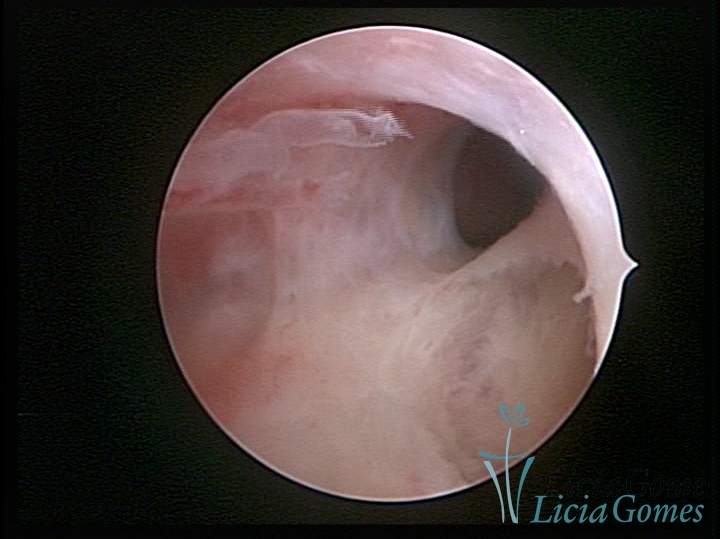

FIBROUS SYNECHIA

Uterine synechiae are scars (adherence) between the surface of the uterine walls, which may occur after the surgical procedure, uterine curettage, or after an inflammatory process in the uterine cavity (endometritis), which may lead to menstrual changes, infertility and obstetric complication such as abortion and premature birth.